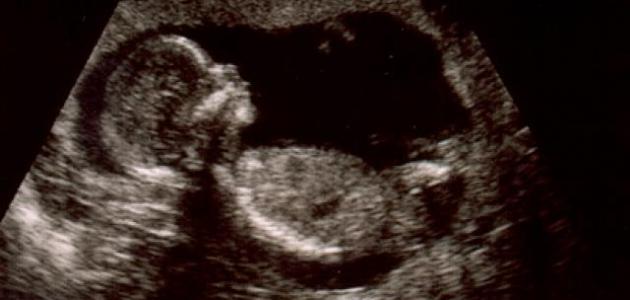

استخدام التصوير بالأمواج فوق الصوتية أو السونار الذي تطوّر تطوراً كبيراً ليوفّر دقة أكبر في قياس وزن الجنين، ويمكن أيضاً قياس محيط البطن لتقدير حجم الجنين داخل الرحم، وفي حالة انخفاض وزن الجنين يجب إجراء العديد من الفحوصات للتأكد من سلامته مثل فحص السوائل حول الجنين، وتخطيط قلب الجنين.